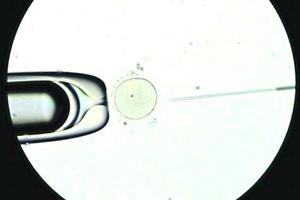

Nace primera guagua con técnica que activa los espermatozoides